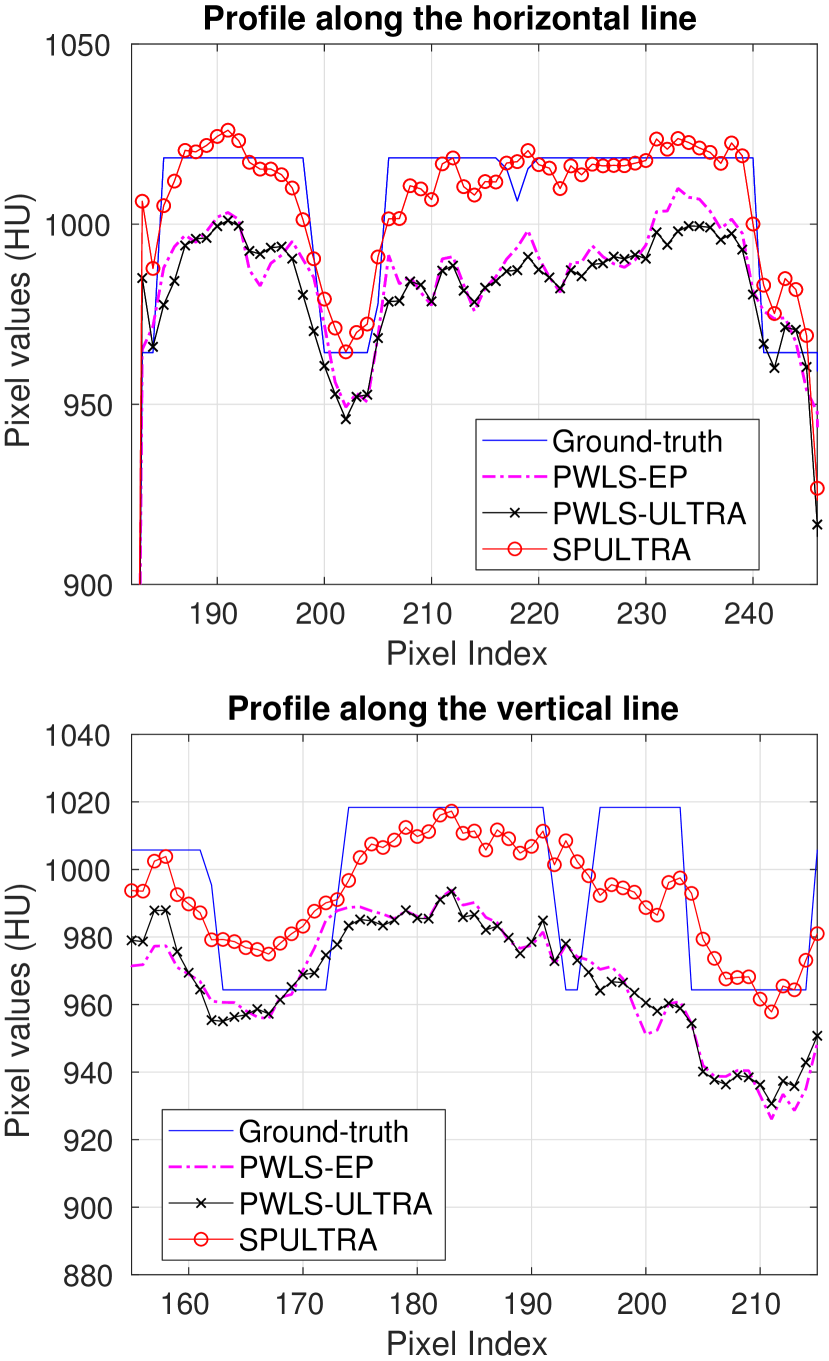

Fig. 4 shows the reconstructed images and the corresponding error images for PWLS-EP, PWLS-ULTRA, and SPULTRA, at and . Compared to the PWLS-EP result, both PWLS-ULTRA and SPULTRA achieved significant improvements in image quality in terms of sharper reconstructions of anatomical structures such as bones and soft tissues, and suppressing the noise. However, the PWLS-ULTRA method introduces bias in the reconstructions, which leads to larger reconstruction errors compared to the proposed SPULTRA method. In Fig. 4, we marked three 3D ROIs in the axial plane, i.e., ROI 1, ROI 2, and ROI 3. Fig. 5 shows the zoom-in images of a 3D plot of ROI 1, and those of ROI 2 and ROI 3 are shown in the supplement. We also plot the evolution of RMSE through the axial slices of the three 3D ROIs in Fig. 6. The figures demonstrate that SPULTRA clearly outperforms the competing PWLS-EP and PWLS-ULTRA schemes.

The above advantages of SPULTRA can be seen more clearly when observing the image profiles. Fig. 7 plots the image profiles for the three methods together with that of the ground-truth image. Fig. 4 shows the horizontal green solid line and the vertical red dashed line, whose intensities are plotted in Fig. 7. It is obvious that the profiles for SPULTRA are closest to the ground-truth among the three compared methods. The gap between the profiles of the PWLS-based methods and the ground-truth shows the bias caused by the compared PWLS methods.